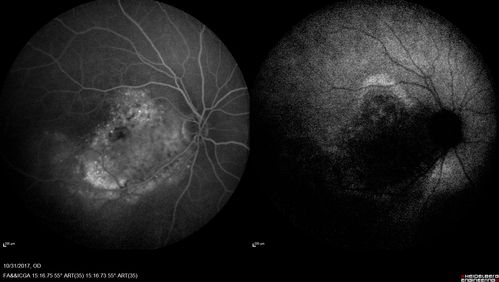

Choroidal Osteoma 13 Year Old

13 year old with 6 months of vision loss right eye and vision of 20/40